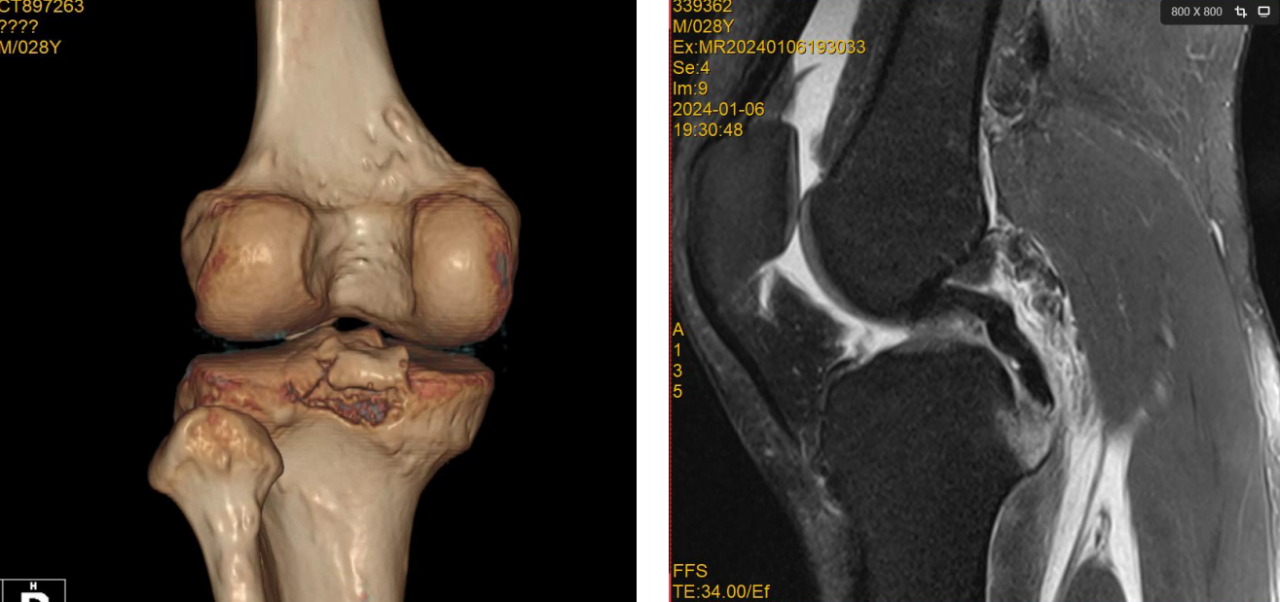

后交叉韧带止点撕脱骨块

1.CT与MRI矢状位骨折块长度(BC);

2.矢状位撕脱骨折前后距与胫骨平台前后距比例(AE/AD);

Ⅰ型:撕脱骨折块BC小于15mm,AE/AD小于1/2;

Ⅱ型:撕脱骨折块BC大于/等于15mm,AE/AD小于1/2,常见;

Ⅲ型:撕脱骨折块BC大于15mm,AE/AD大于或等于1/2;

ⅢA型:多块撕脱骨折块,BC大于15mm,AE/AD大于1/2;

ⅢB型:骨折块合并半月板撕裂,BC大于15mm,AE/AD大于或等于

1/2。

ⅢC型:髁间棘陈旧性撕脱骨折, BC大于15mm,AE/AD大于或等于